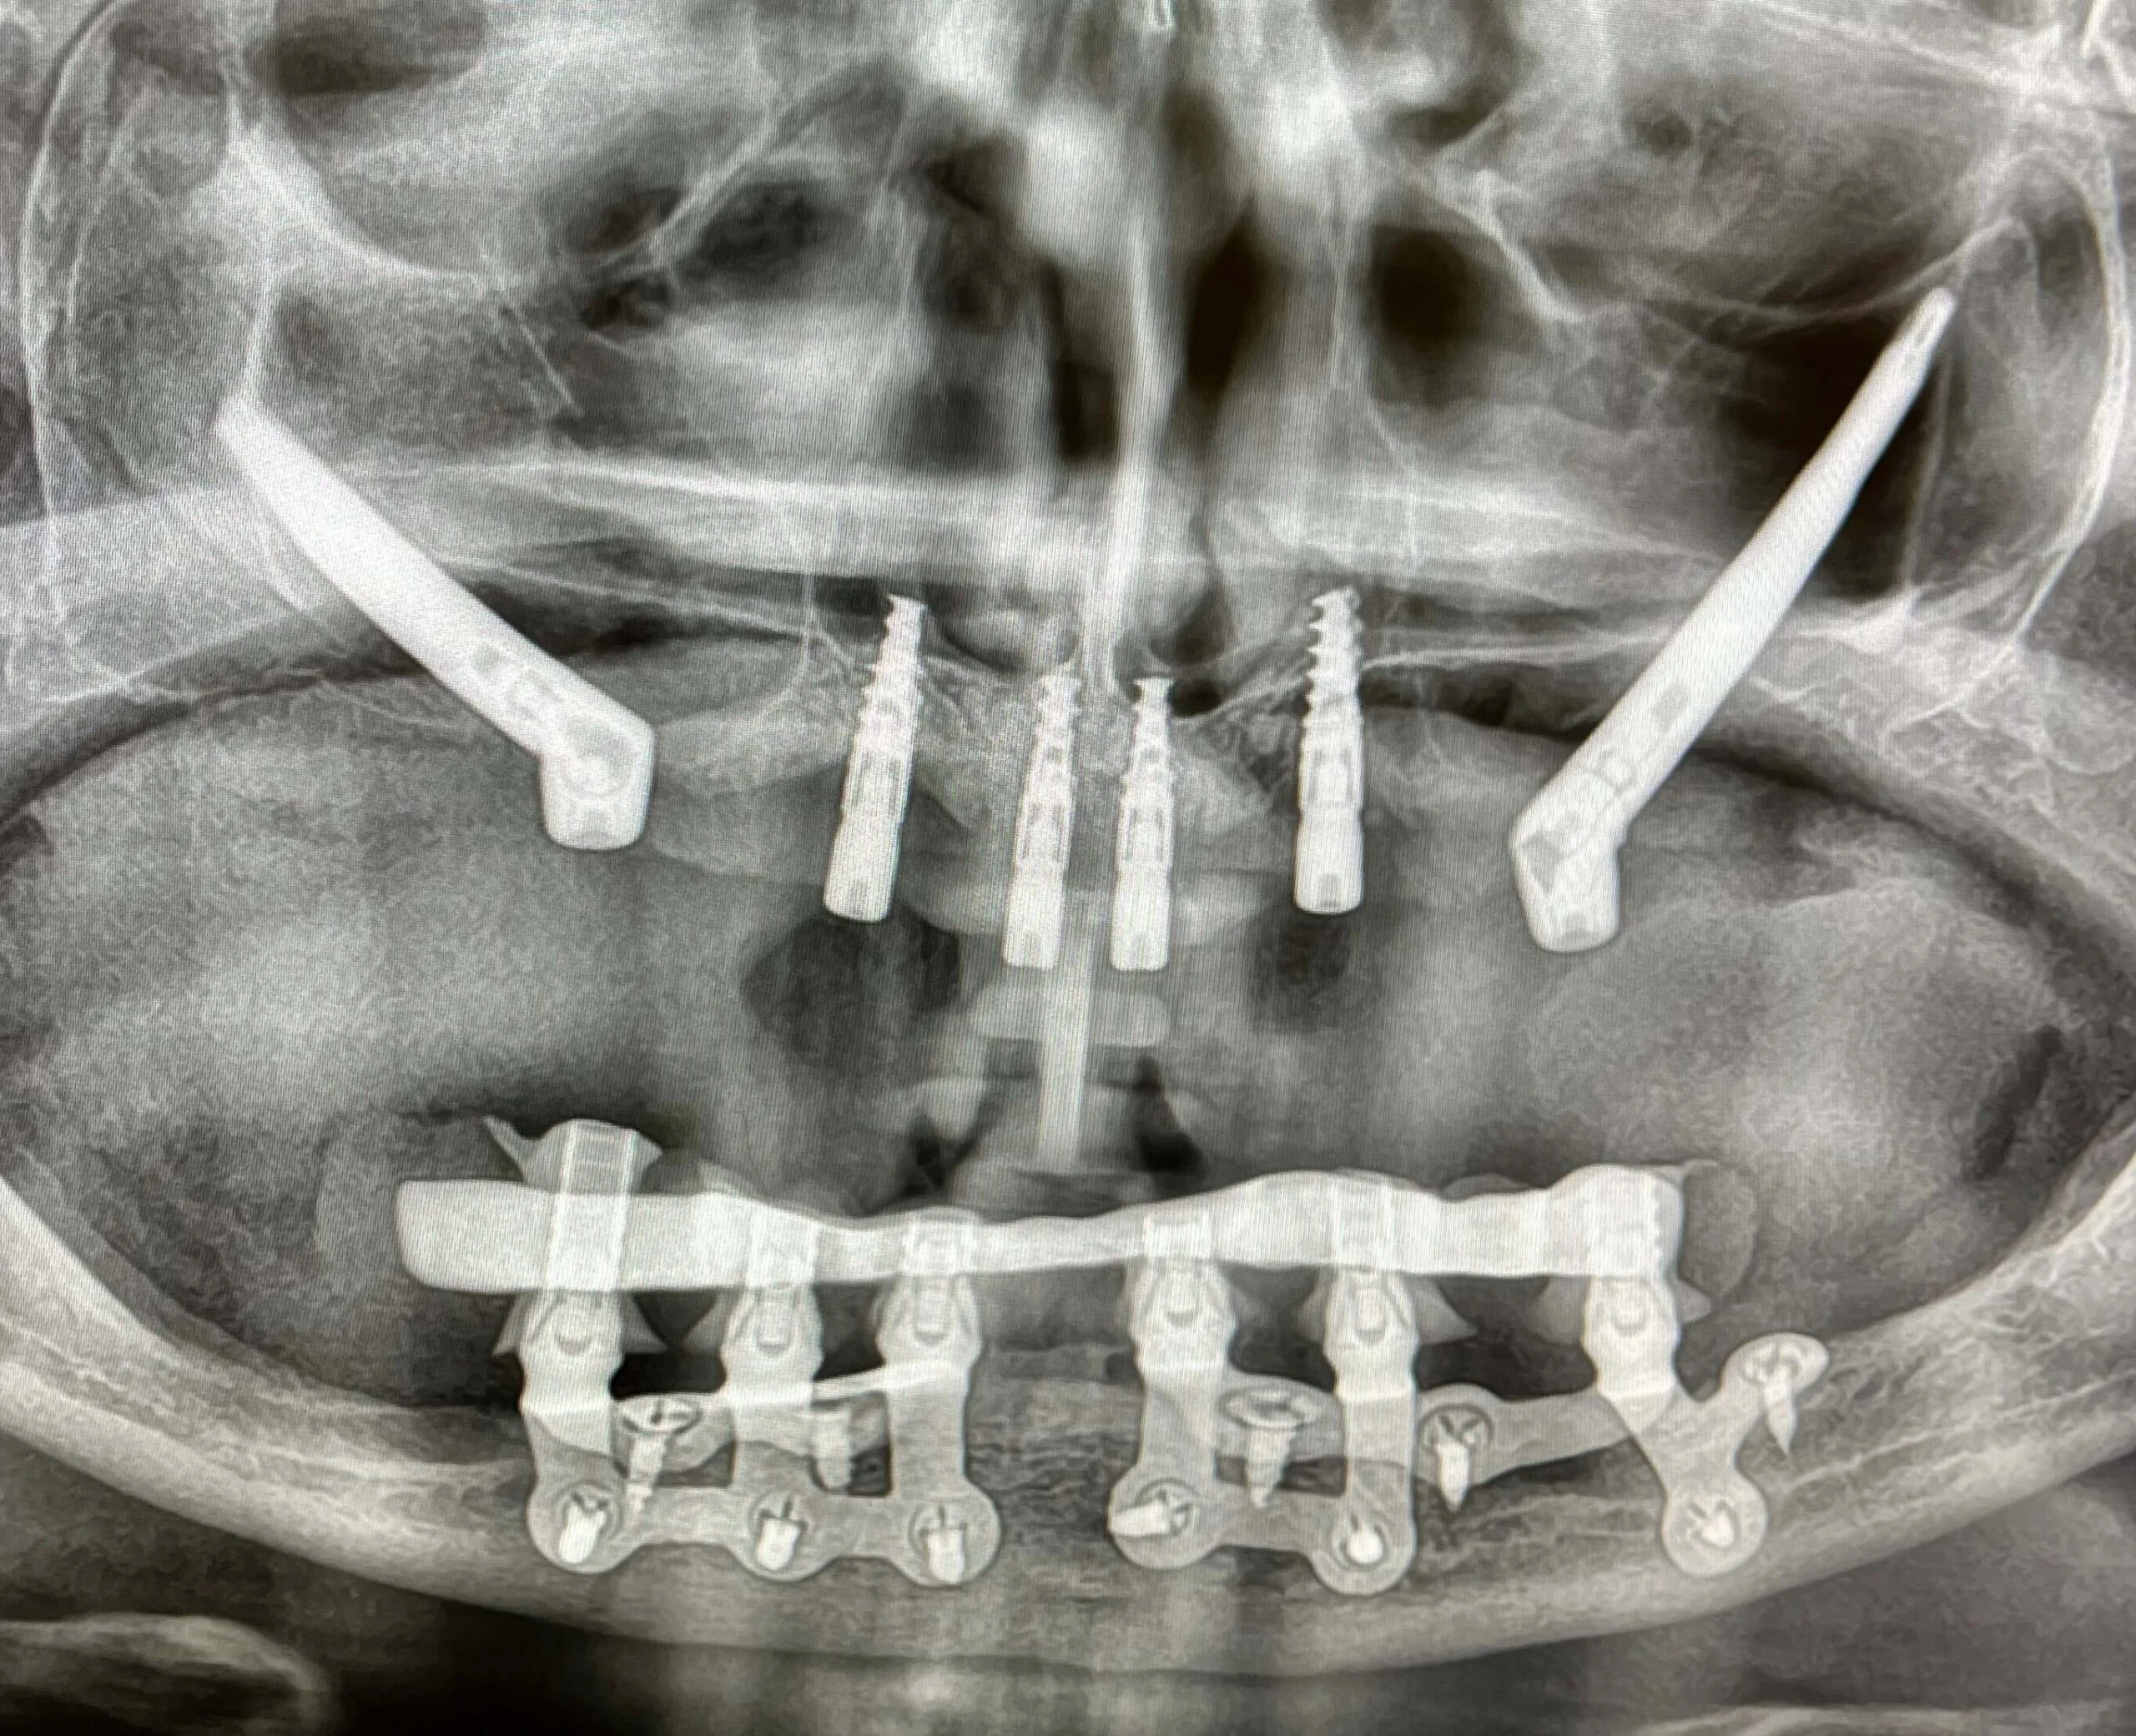

Pacjent 1

Dwa implanty zygomatyczne i 4 implanty klasyczne w szczęce, implanty podokostnowe w żuchwie.

Przykład implantologicznej przy całkowitym zaniku kości w żuchwie przy pomocy implantów podokostdnowych IUXTA 3D